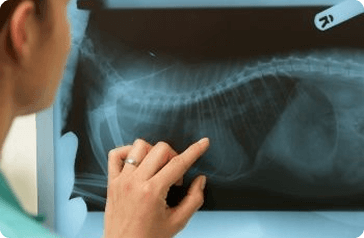

Röntgen

Kórházunkban a legkorszerűbb digitális röntgen készülékekkel végezzük a vizsgálatokat. Ortopédiai szűrővizsgálatokhoz (csípő, könyök, váll - MKOE), belgyógyászati diagnosztikához, valamint traumatológiai és ortopédiai vizsgálatokhoz alkalmazzuk.